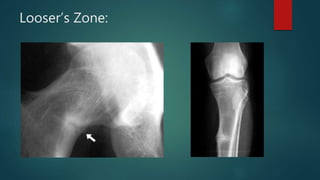

Looser’s Zone:

X-RAYS  Long bones: bowing thickeningof cortex, narrowing of medulla honey combed or spongy, large dense bone looser’s zone of transformation